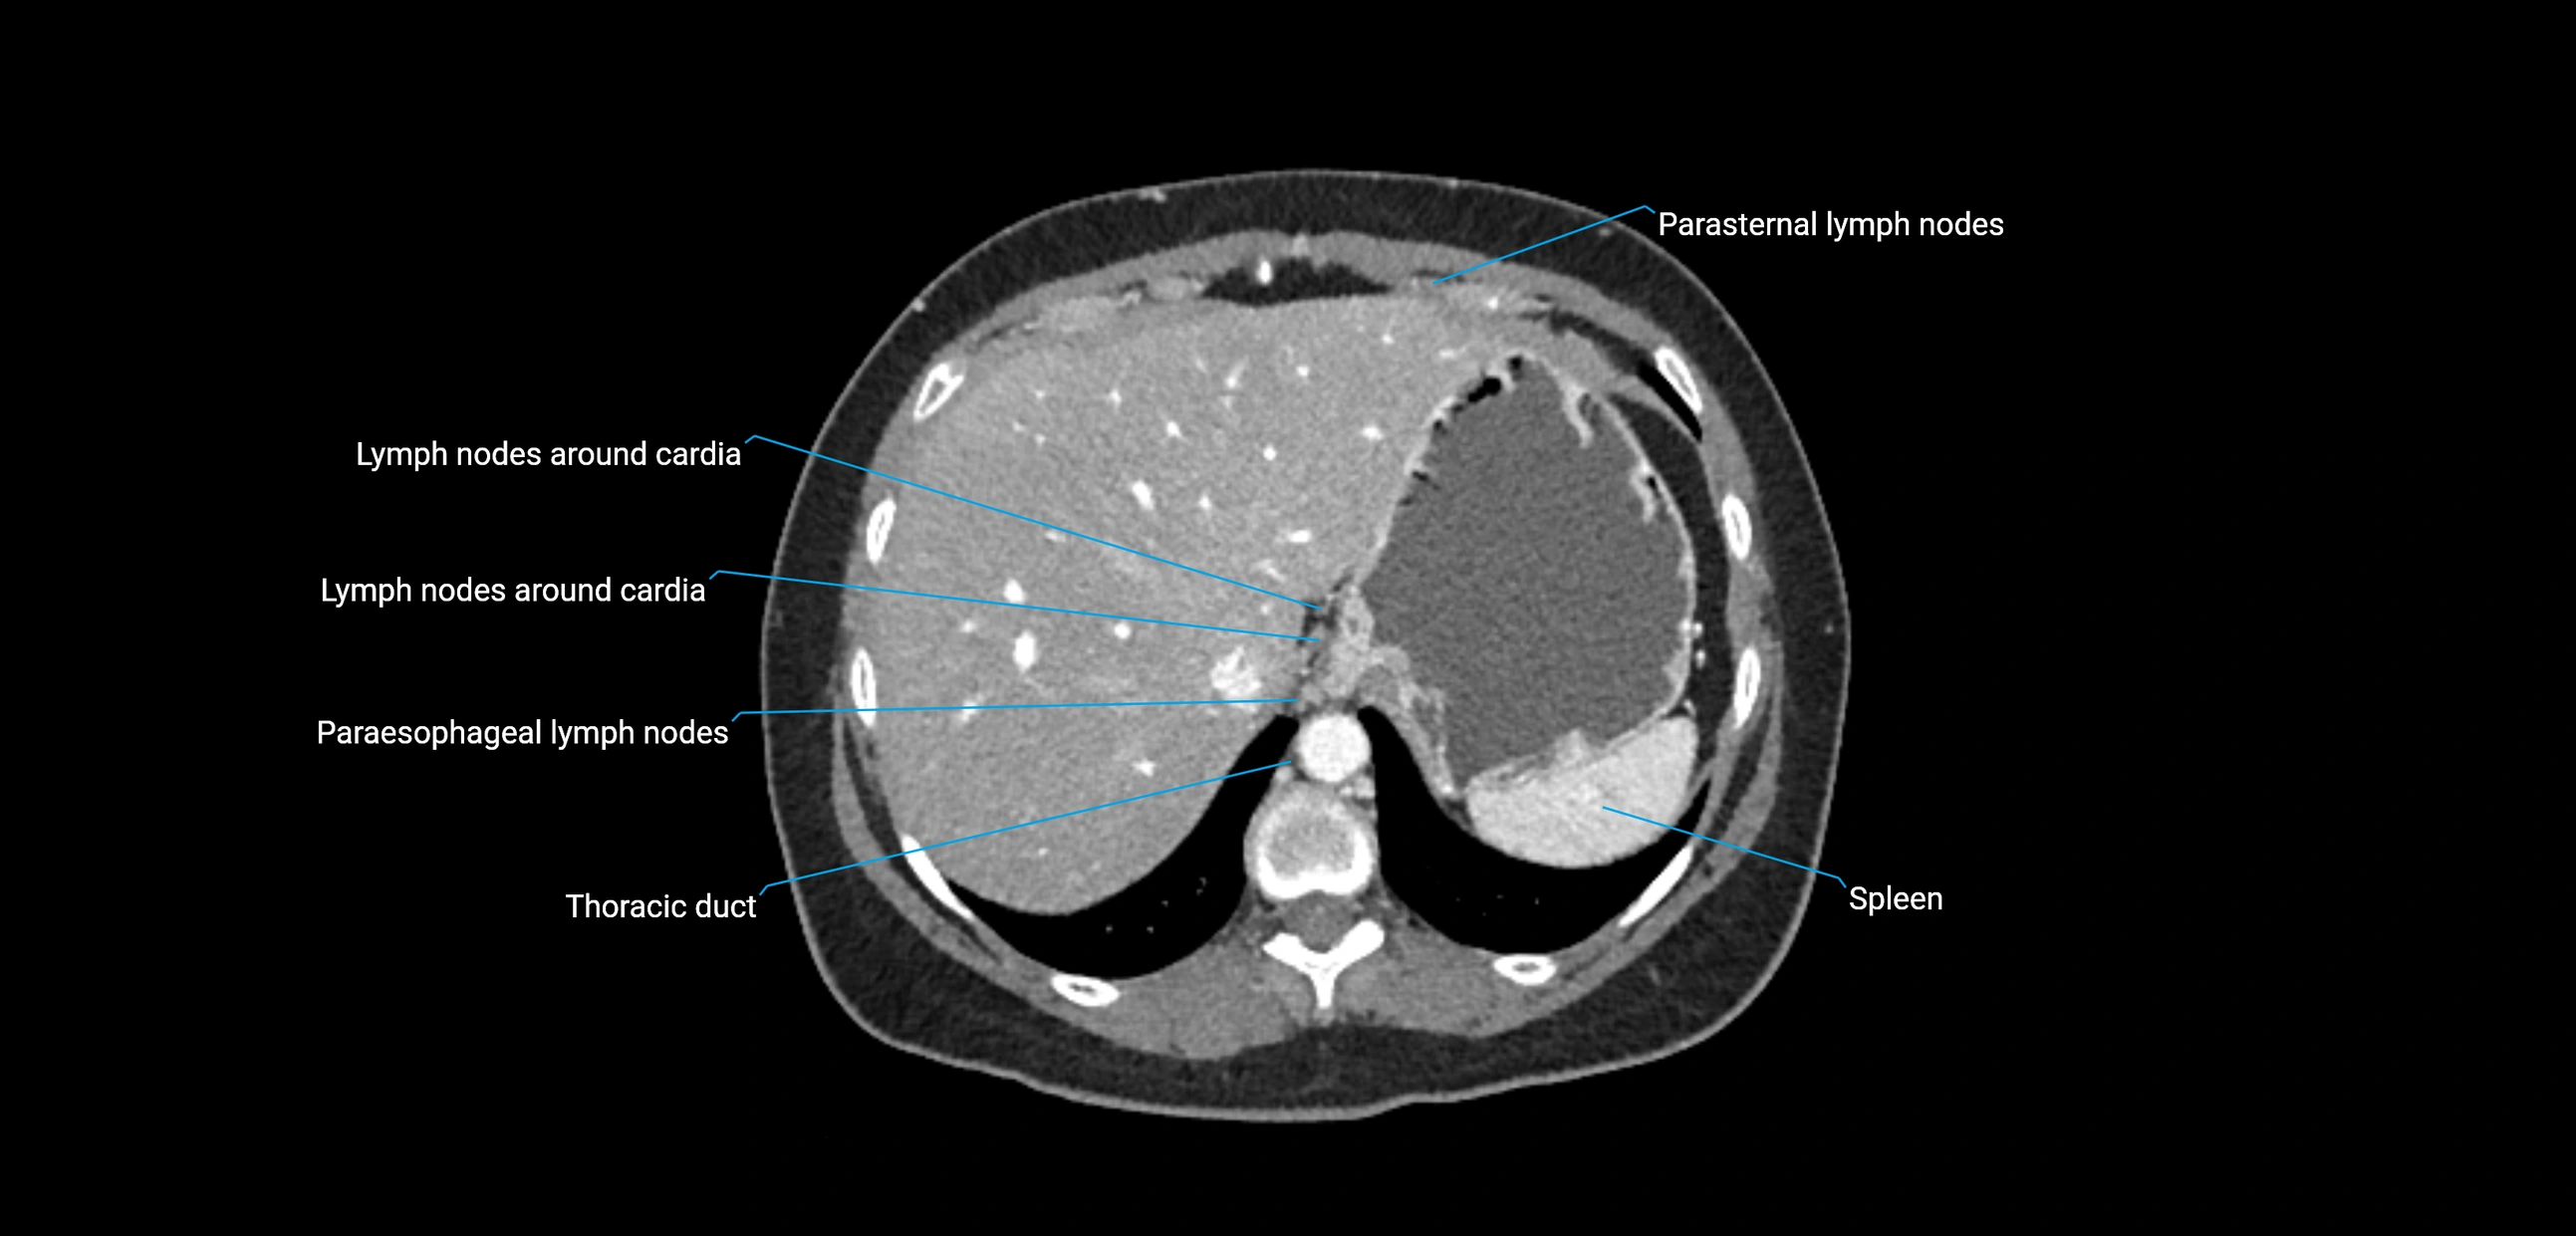

These nodes receive lymph from a wide range of abdominal and pelvic structures. Specifically, they drain lymph from the kidneys, suprarenal glands, gonads (testes/ovaries), uterus, uterine tubes, and pelvic organs, before converging into the lumbar lymphatic trunks, which terminate in the cisterna chyli → thoracic duct.

• Provide a major pathway to the cisterna chyli and thoracic duct